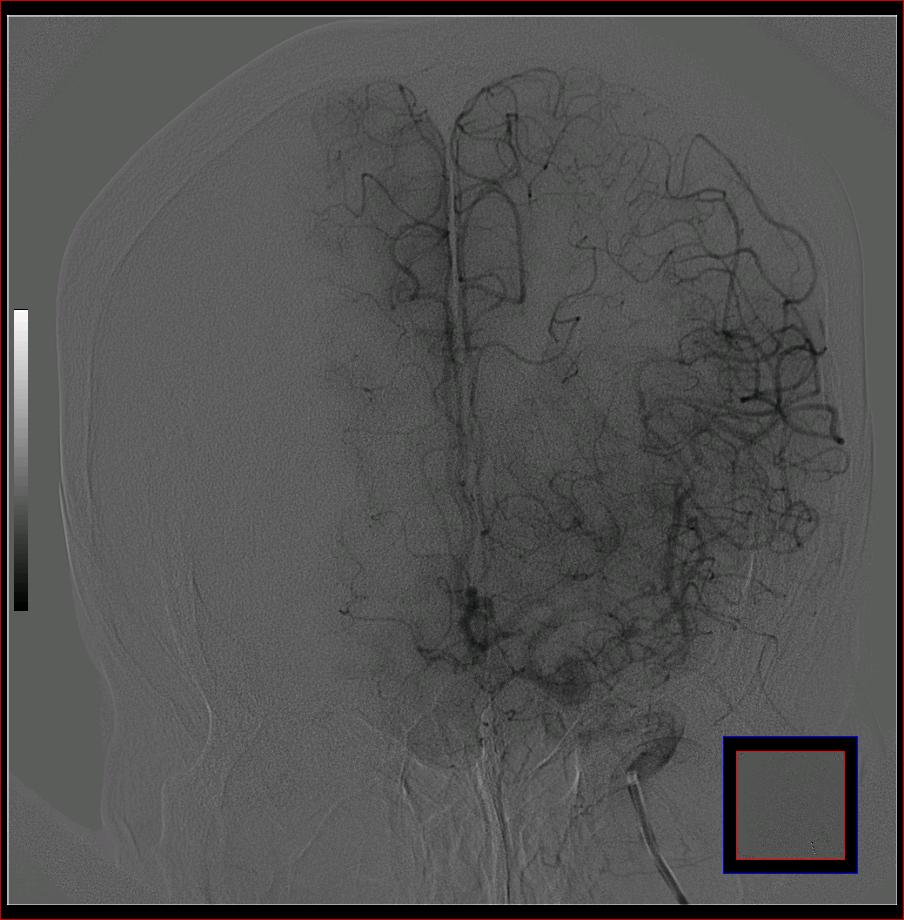

标题: DSA0121:脑血管造影

男,65岁,肢体无力。

大脑前动脉a2段动脉瘤.

前交通或稍远端动脉瘤要仔细查,左大脑中动脉狭窄要鉴别,有可能是痉挛,因为造影导管插得稍深啦。其它就是供血动脉变异较大

烟雾病